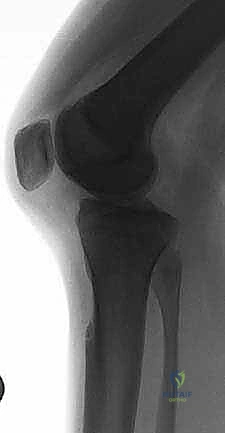

- الأشعة السينية (X-rays): لاستبعاد وجود كسور عظمية، خاصة كسور الانقلاع (Avulsion fractures) حيث ينفصل الرباط حاملاً معه قطعة من العظم.

- أشعة الرنين المغناطيسي (MRI): هو المعيار الذهبي لتأكيد التشخيص. يوضح الرنين المغناطيسي بدقة موقع التمزق، درجته، وحالة الغضاريف الهلالية والأربطة الأخرى.